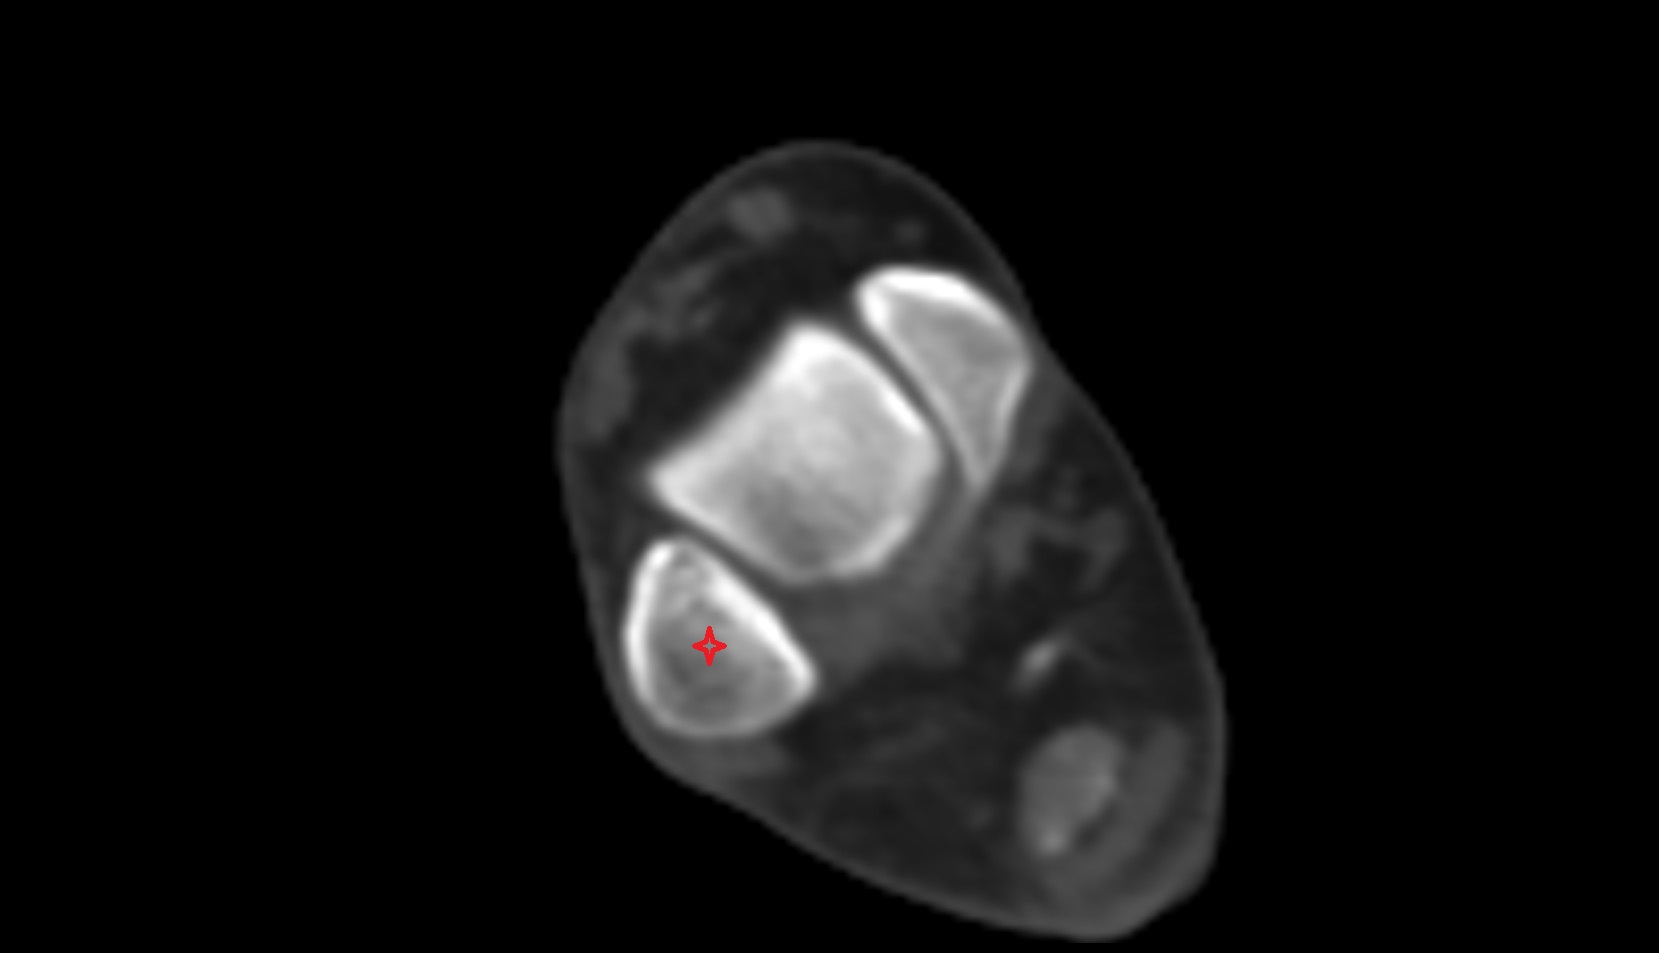

- Calcaneus

- Sustentaculum tali

- Medial malleolus

- Lateral malleolus

- Ankle joint

- Talocalcaneal joint